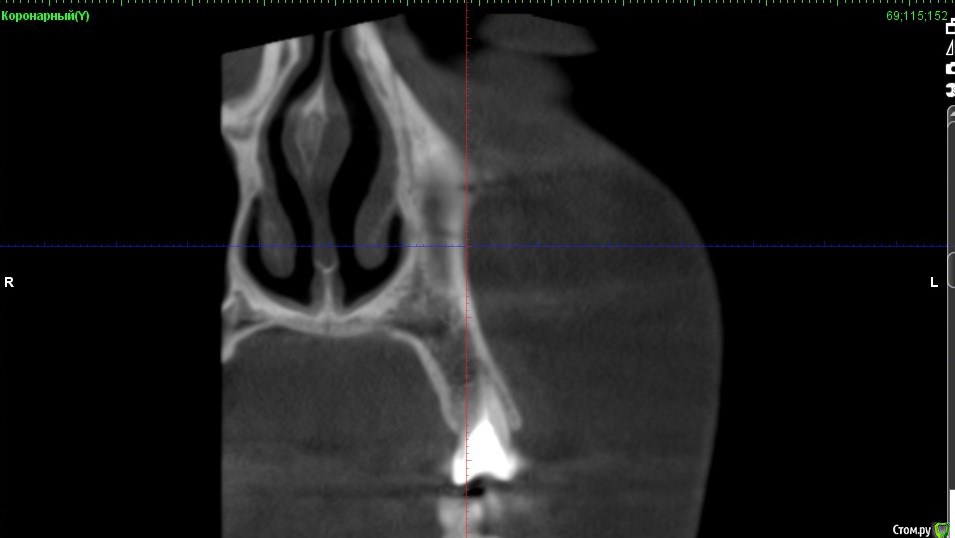

Verasss Опубликовано 8 октября, 2016 Автор Поделиться Опубликовано 8 октября, 2016 КТ от 08.09. Извините, что в таком виде, надо менять ОЗУ. Ссылка на комментарий

DmitrySH Опубликовано 8 октября, 2016 Поделиться Опубликовано 8 октября, 2016 В таком виде КТ малоинформативно. Но гайморита нет. Ссылка на комментарий

Verasss Опубликовано 28 октября, 2016 Автор Поделиться Опубликовано 28 октября, 2016 Добрый вечер! Ещё раз попытаюсь прикрепить скриншоты КТ от сентября. Если качество совсем не устраивает, подскажите, пожалуйста, какие сделать снимки?К сожалению, программа не позволяет вывести снимки на полный экран и заскриншотить в более хорошем качестве. Ссылка на комментарий

Verasss Опубликовано 28 октября, 2016 Автор Поделиться Опубликовано 28 октября, 2016 и еще Ссылка на комментарий